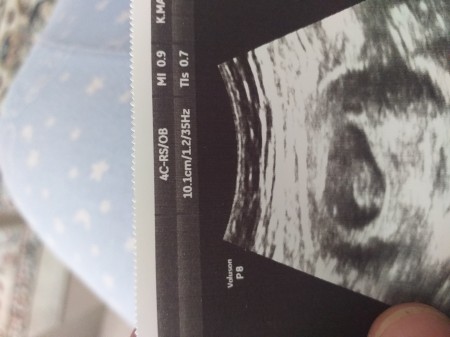

Merhaba kızlar adet tarihime göre 8 +5gunluk gebeyim doktor bugün 1 buck aylık dedi ben şaşırdım soramadmda birdaha gdicm snda ama şuan merak ettim kalp atsiimiz var çok şükür

Gebelik haftası 8+5

9 hafta bebek boyundan anlasiliyor ve boyuda guzel masallah 2. Ayı bitirmissin

Cnm elleri kolları görünüyordu ama doktor böyle çok yakından çekti yoksa çok şükür var